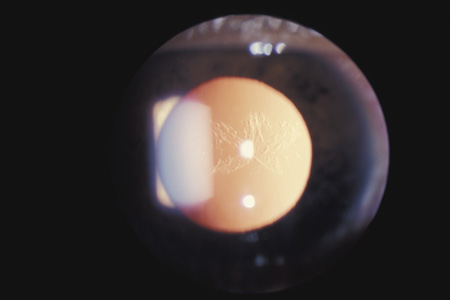

In injuries severe enough to cause a full-thickness corneal rupture, the wound usually crosses the limbus into the adjacent sclera. Exceptions are eyes that have had radial keratotomy, cataract surgery, or corneal transplantation, even years before the trauma.36–38 GLAUCOMA Acutely, the intraocular pressure may be normal, increased, or decreased. Aqueous outflow may be decreased because of angle recession, inflammatory trabeculitis, or hyphema. On the other hand, ciliary body injury tends to decrease aqueous inflow. The intraocular pressure depends on the balance of these factors. In patients who have large hyphemas, the pressure may rise abruptly. Therefore, it must be checked at regular intervals. It is especially important to monitor the intraocular pressure in hyphema patients who have sickle cell disease, be it homozygous or heterozygous. Unlike normal erythrocytes, sickled erythrocytes cannot pass through the trabecular meshwork and tend to occlude it, raising intraocular pressure. This, in turn, can cause central retinal artery obstruction even if the pressure is only in the high twenties or low thirties. Prompt paracentesis followed by surgical evacuation can restore vision.39 Late glaucoma can also develop, even years after the initial injury. Autopsy studies have found three ways by which the trabecular meshwork can be obstructed: proliferation of corneal endothelial cells and Descemet's membrane, proliferation of fibroblasts, and peripheral anterior synechiae (presumably from inflammation or from organization of blood in the angle for more than 7 days).40 Other possibilities are direct damage to the trabecular meshwork and damage to the ciliary muscle with reduced traction on the scleral spur. The risk is greatest in patients who have severe anterior segment damage such as cataract, angle recession, iris damage and displacement of the lens.41 Nine percent of patients with angle recession develop permanent glaucoma.42 If trabeculectomy is required, some authors recommend antimetabolites because the failure rate in patients with angle recession is greater than it is in patients with typical open angle glaucoma.43 LENS When the lens is struck by the cornea or by a strong shock wave, a transient anterior subcapsular cataract, known as a rosette cataract, may develop (Fig. 6). Repeated trauma, as in boxers, often causes posterior subcapsular cataract. Blunt trauma can also result in rupture of the anterior or posterior capsule.44,45 In severe cases, iridodonesis or a bead of vitreous in the anterior chamber signals a subluxed lens. Dislocation may also occur (Fig. 7). It is important to remember that ocular trauma is common, but lens dislocation is rare. Therefore, in patients with a dislocated lens, the clinician should always rule out predisposing causes such as Marfan's syndrome, homocystinuria and syphilis. In rare cases the lens itself can rupture and cause phacolytic glaucoma.